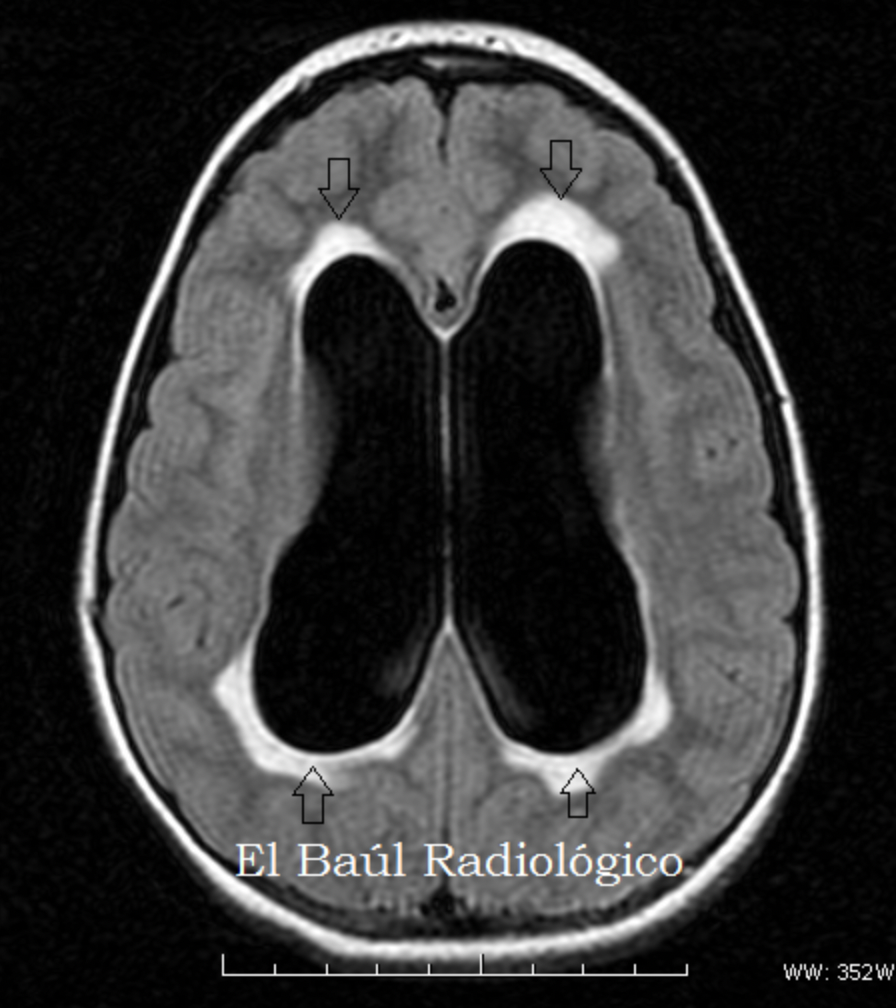

El exudad transependimario puede visualizarse como hiperintensidad periventricular en las secuencias:

A

T2

FLAIR

El aumento de la PIC (como en la hidrocefalia) da extravasacion transependimaria de LCR en el tejido cerebral que provoca:

Daño cerebral

Atrofia inducida por presion

Se da este tipo de edema en hidrocefalia aguda:

Edema transependimario